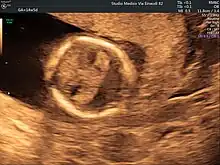

Ultrasound scan of a fetal head at 14 weeks of pregnancy with partial absence of the midline

Holoprosencephaly is typically diagnosed during fetal development when there are abnormalities found on fetal brain imaging, however it can also be diagnosed after birth. The protocol for diagnosis includes neuroimaging (Ultrasound or fetal MRI prior to birth or Ultrasound, MRI or CT post birth), syndrome evaluation, cytogenetics, molecular testing, and genetic counseling.[3]